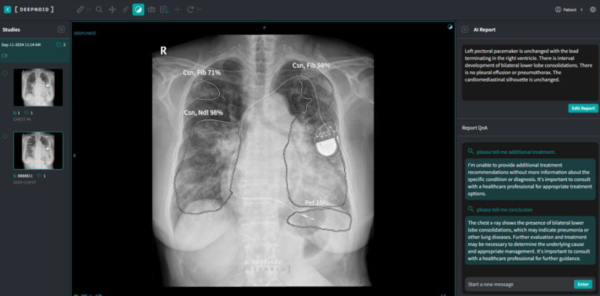

딥노이드의 M4CXR은 흉부 X-ray 영상을 분석해 판독문 초안을 생성하는 거대 언어 모델(LLM)로 설계된 클라우드 기반의 의료 AI 솔루션이다. 연구를 통해 M4CXR은 흉부 X-ray 진단 시 실제 의료현장에서 임상의의 역량을 강화하는 보조 도구로 적합함을 입증했다.

연구는 의료 AI 관련 전문가인 인하대병원 영상의학과 이로운 교수의 주도로 진행됐다. M4CXR과 Chat GPT의 판독 결과를 ▲정확도 ▲위양성 ▲위치 오류 ▲개수 오류 ▲환각 등 다섯 개 지표로 평가했을 때, M4CXR은 모든 평가 항목에서 ChatGPT보다 일관되게 우수한 성능을 보였다. 특히 위치 정확성(76-77.5%)에서 ChatGPT(36-36.5%)를 크게 앞섰다. 진단 정확성 측면에서도 M4CXR(60-62%)은 ChatGPT(42-45%)보다 우수했다.

연구 결과 M4CXR은 전문 의료 환경에서 활용하기에 적합했으며, 범용 AI인 ChatGPT에 비해 우수한 성능을 나타냈다